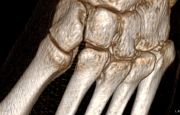

5. Fracture of the left tarsometatarsal joint in a 33-year-old male.

Treatment: Open reduction internal fixation

I. Before surgery, 3D reconstruction of CT scan indicates the Lisfranc injury II. Post-surgery, anteroposterior view of foot with the metal work III. Post-surgery, lateral view of foot with the metal work